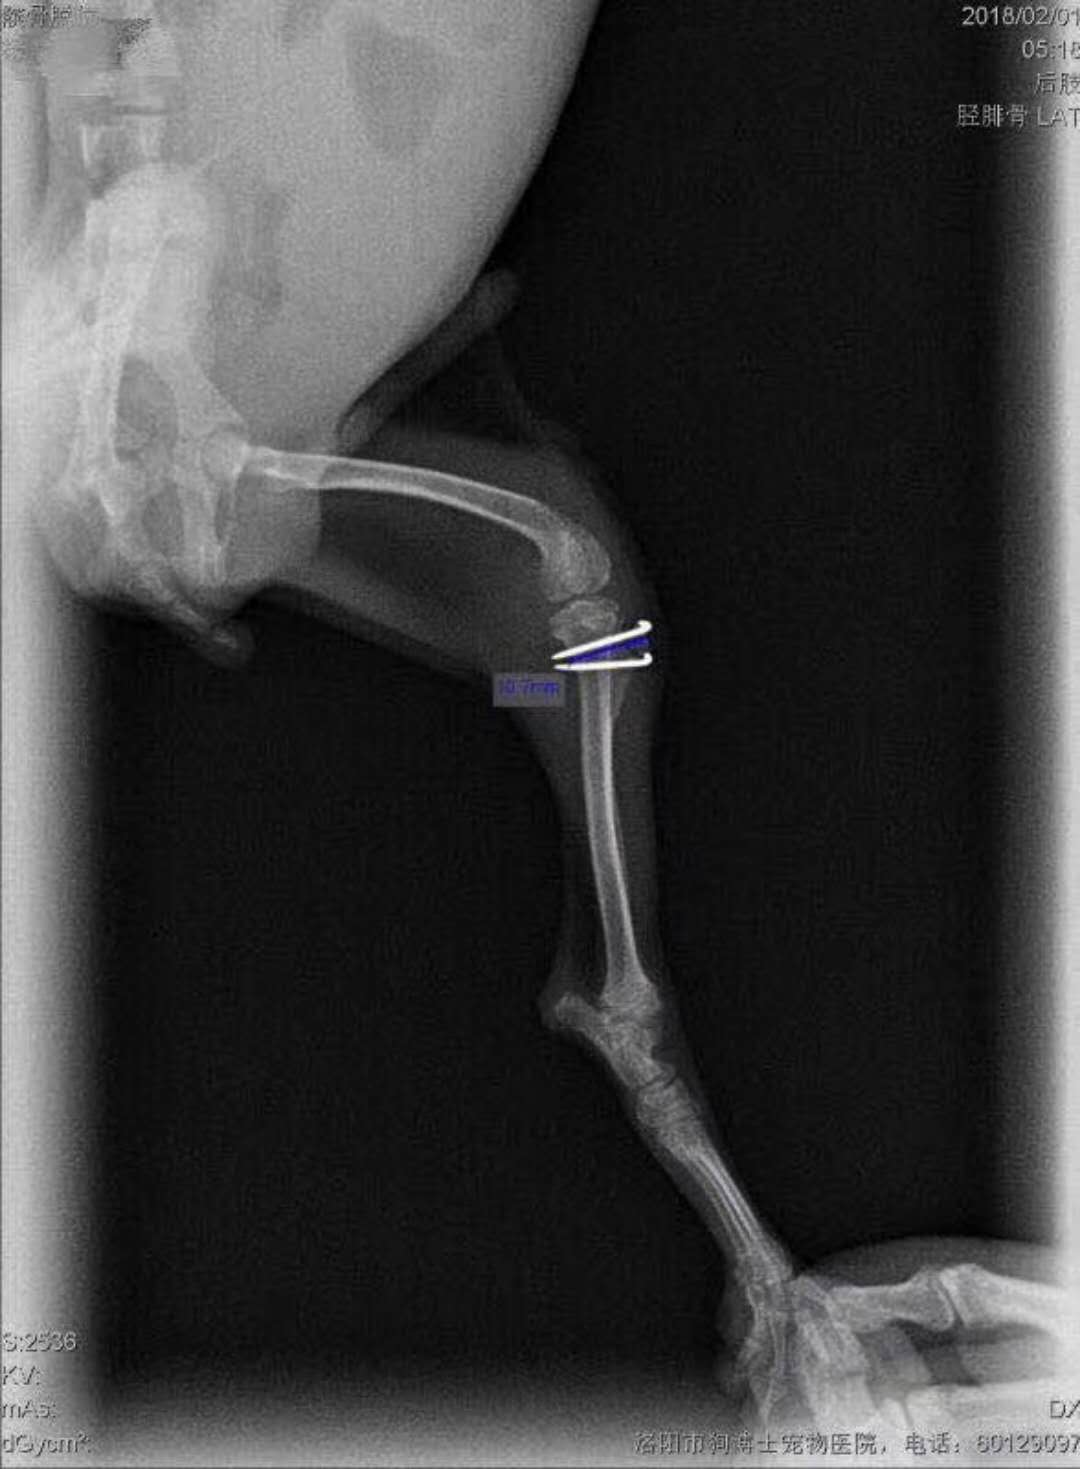

微小泰迪髕骨移位手術(shù)再一例:微小體泰迪,雙側(cè)髕骨移位,其中左腿嚴重,為4級移位,走路時難以負重,來院實施滑車溝再造術(shù)、脛骨粗隆移位術(shù)、及髕骨周圍軟組織修復術(shù)。手術(shù)順利,狗狗很頑強,麻醉剛剛蘇醒,走路姿勢就恢復正常了,見倒數(shù)第三張圖,住院護理中。